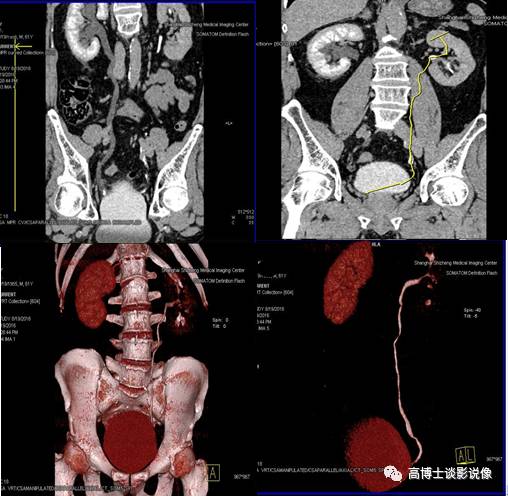

十、CT尿路造影VRT重建

CPR重建整体、全程显示输尿管结石及梗阻情况。去骨或非去骨VR重建,整体、直观显示整个泌尿系的轮廓、大体形态及梗阻情况,初步判断肾脏功能情况,同时整体显示全腹部动脉的走行、形态及有无异常。此例显示:右输尿管末端膀胱入口处结石伴右肾盂、右输尿管全程积水扩张,右肾显影功能延迟。